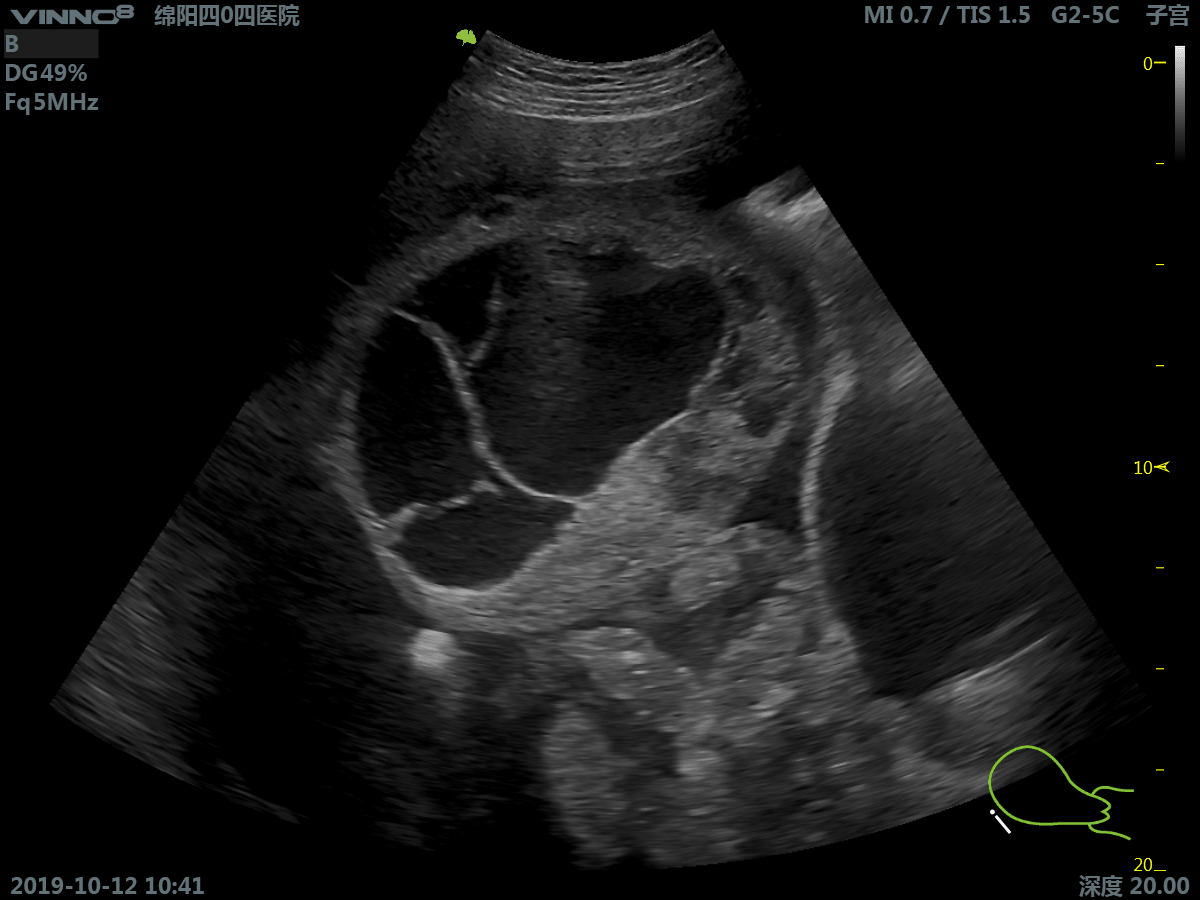

- акушерство/внутриутробное развитие

- гинекология

- трансвагинальное обследование

1. B-режим. Позволяет получить двухмерное плоскостное изображение на некоторой глубине расположенных рядом структур и их движение во времени.

17. 3D. Режим получения трехмерного акустического изображения.

18. Real time 3D(4D) – B (HARMONIC) Режим трёхмерного (четырехмерного, четвертая ось - время) сканирования в реальном времени совместно с режимом тканевой гармоники.